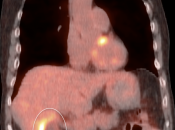

Initial Staging of Gallbladder Carcinoma:

- While PET/CT can detect the primary lesion, its true utility lies in the detection of regional nodes and distant metastatic disease.

- Distant Disease: Most commonly to the liver, lung and brain.